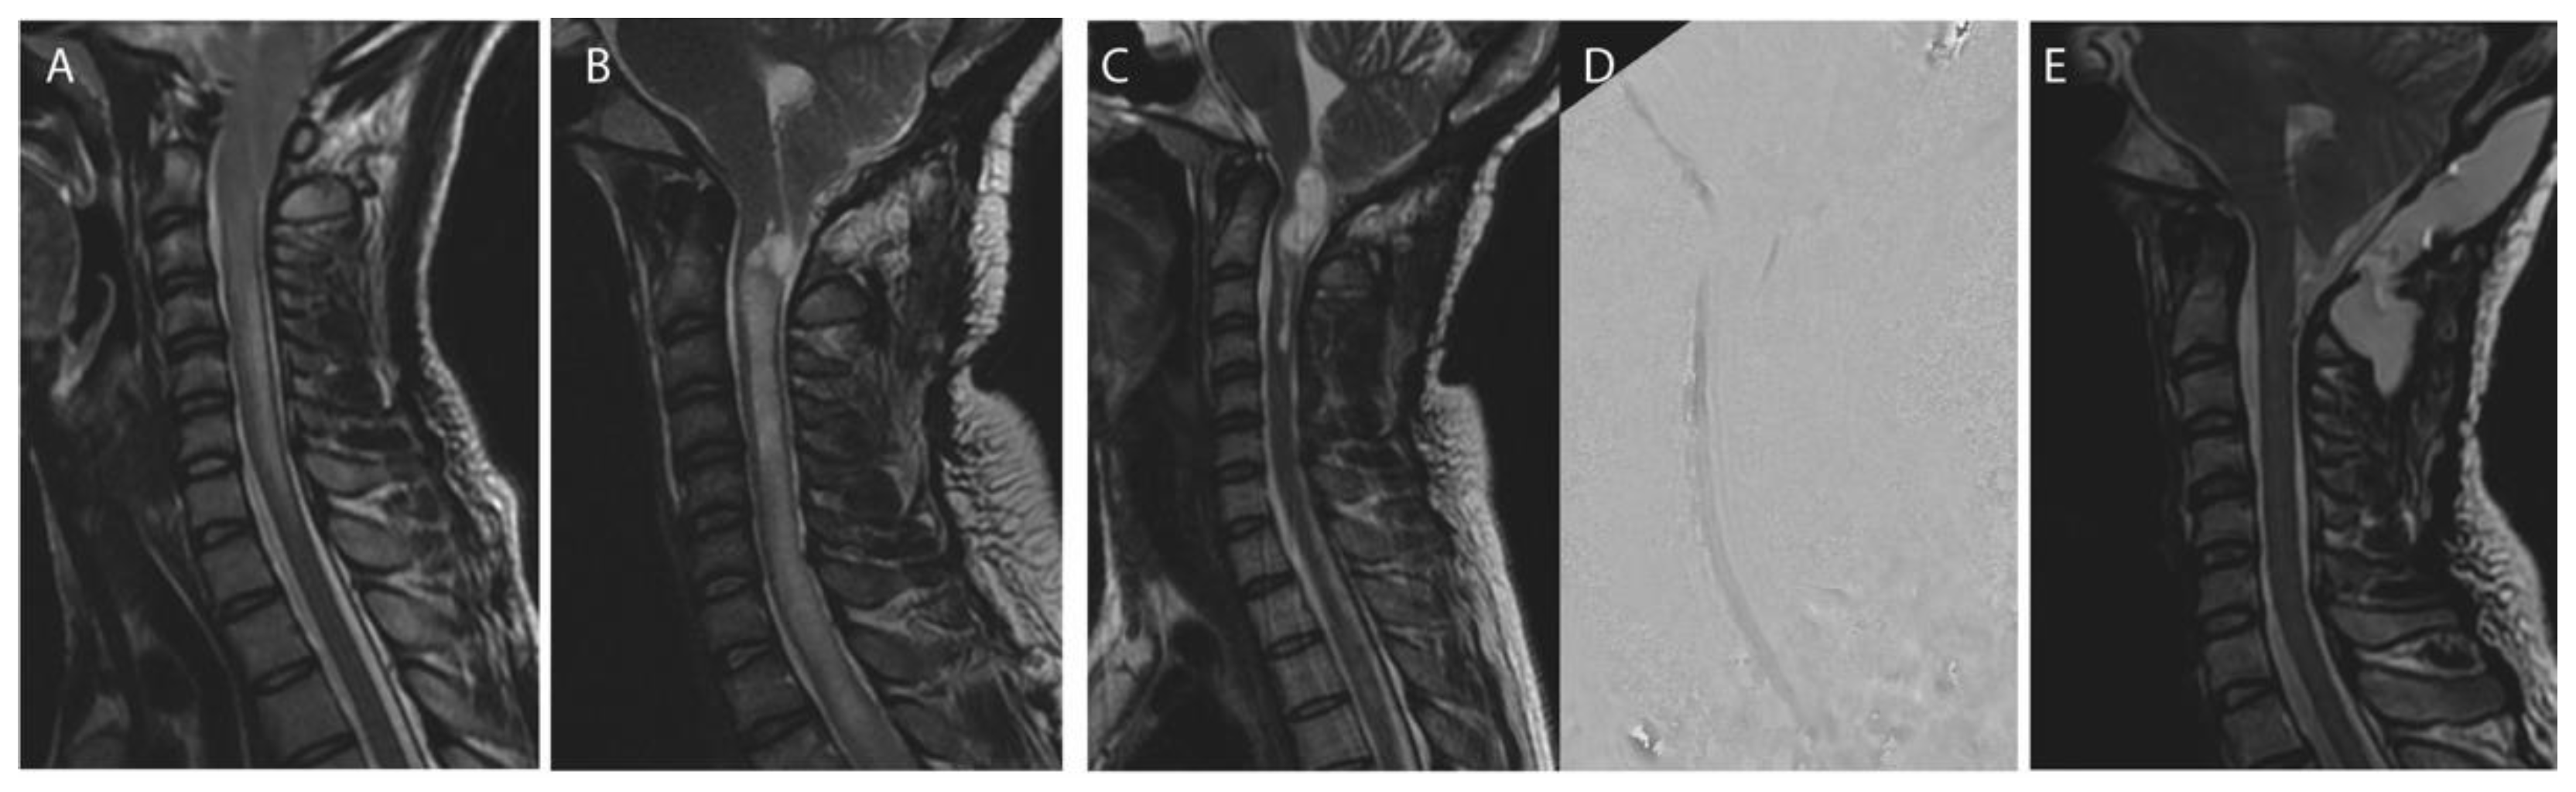

Figure 3. Shunting revision after Chiari decompression failure. Case of a 20 years-olf male patient with a Chiari I malformation with syringomyelia and associated scoliosis before index decompression surgery (A). Extensive foraminal arachnoiditis was observed during surgery, confirming the discrepancy between moderate tonsillar herniation and holocord syringomyelia. Persistant (B) and circulating (C) syrinx with no CSF flow at the craniovertebral junction (C). CSF diversion was performed: resolution of the syringomyelia (D) after placement of a syringo-peritoneal catheter at the lower extremity of the syrinx (E).

Non-foraminal CSF diversion was performed in 9 patients (25.7%) undergoing a first revision procedure and consisted in either ventriculo-peritoneal shunt (n = 3), a syringo-peritoneal shunt (n = 4), lumbo-peritoneal (n = 1) or meningocele-peritoneal (n = 1; Table 2, Figure 3).